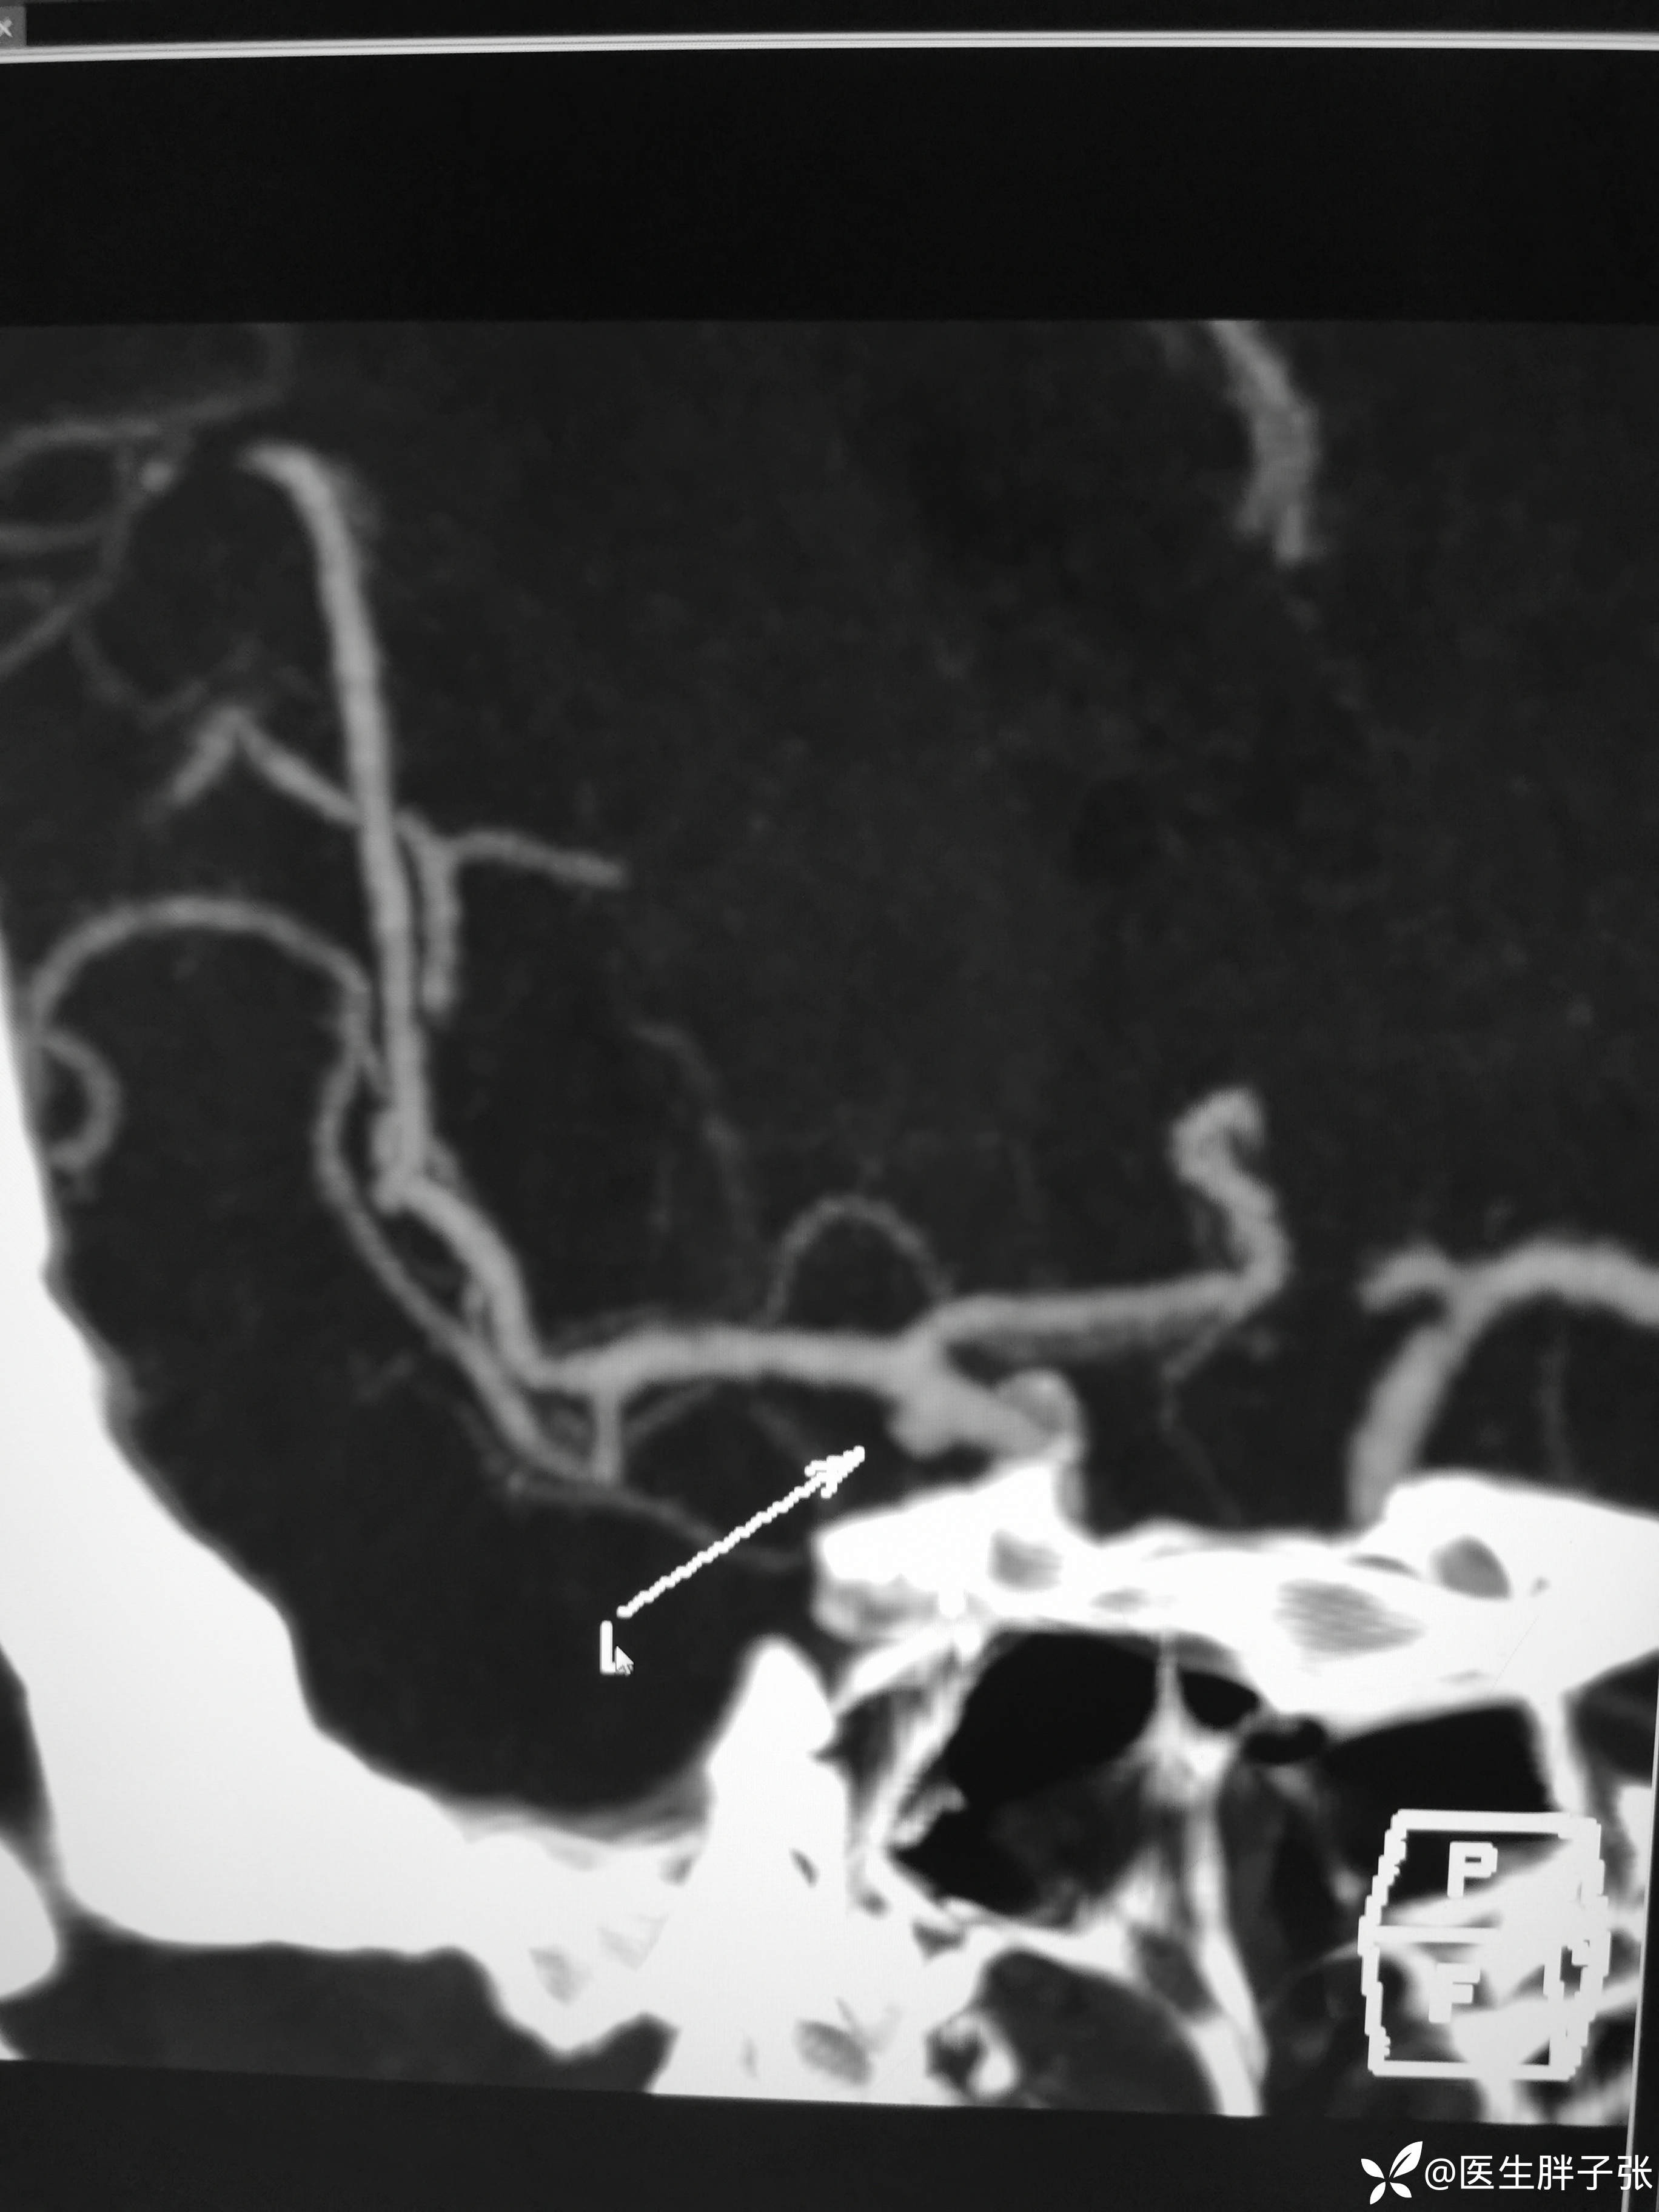

头颈部CTA提示左侧椎动脉闭塞、右侧椎动脉开口中度狭窄、左侧颈内动脉动脉瘤。

MRV:右侧侧窦纤细,充盈浅淡,上矢状窦后部成窗。